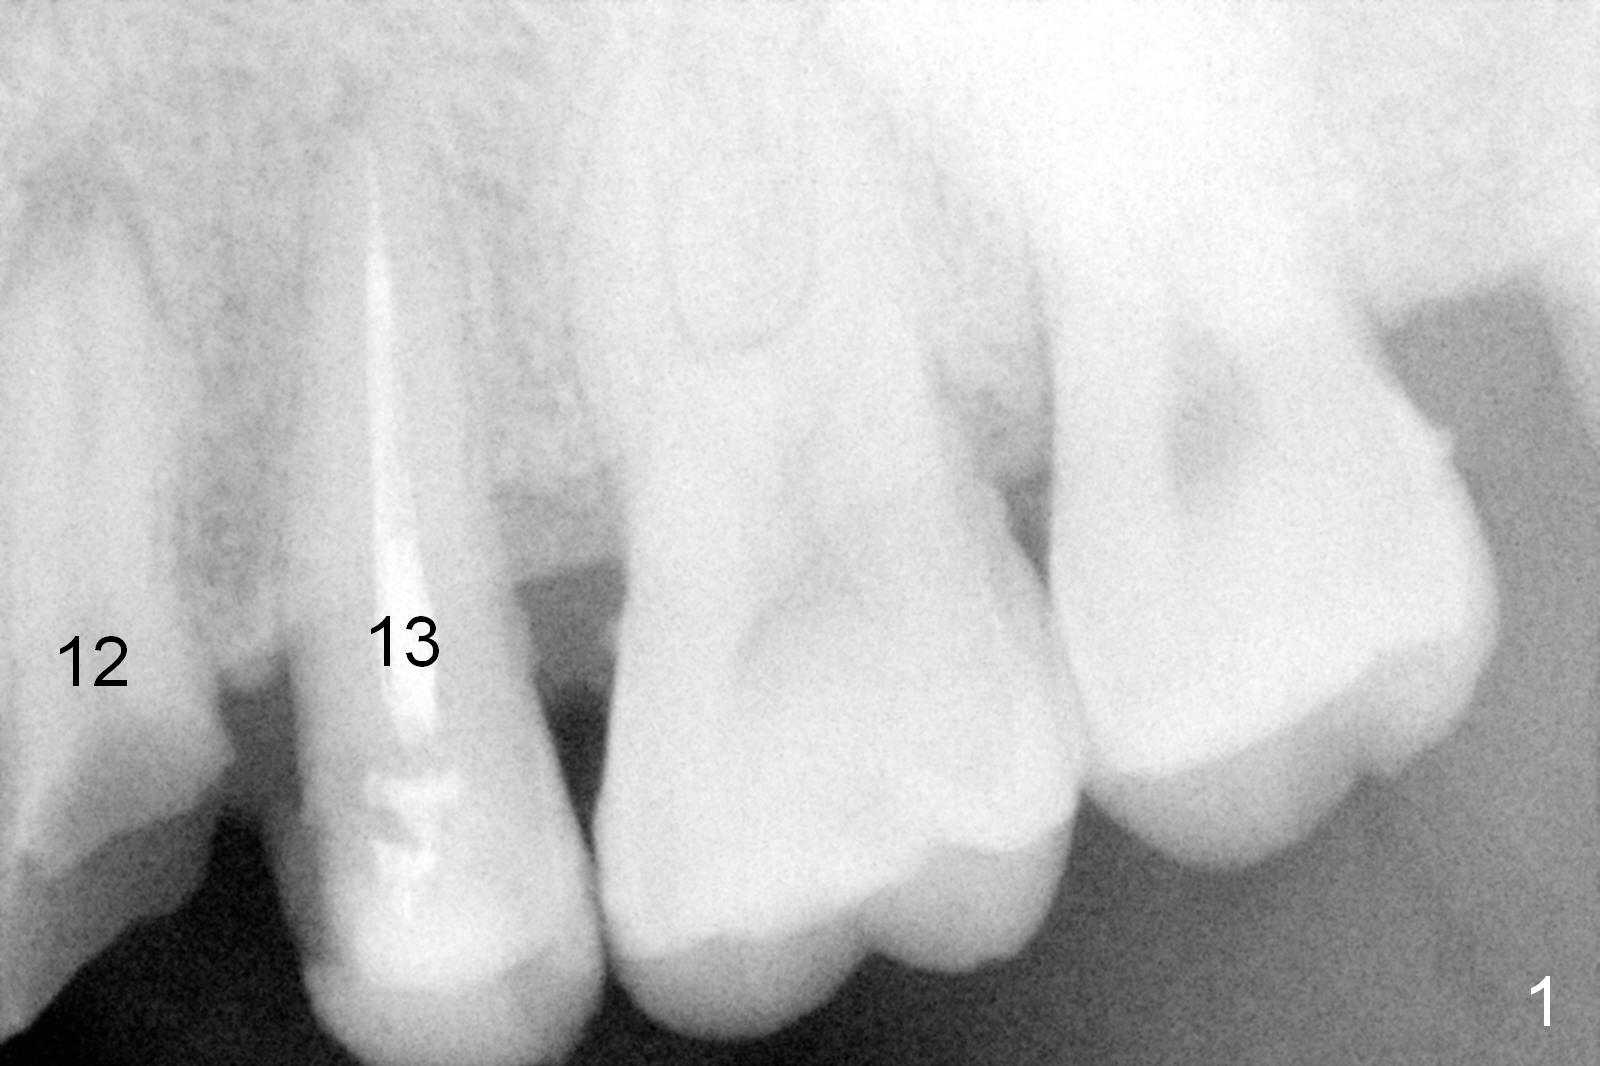

A 45-year-old man presented to our office 8 years ago (Fig.1,2) and got work done somewhere else. He returned yesterday with chief complaint "I might swallow my crowns". Exam shows residual roots at #12,13 (Fig.3,4). The patient has strong jaw bone, suggesting that the bone density is high. Either bone- (Fig.5) or tissue- (Fig.6) level implants will be placed. By time sequence, this case will be assigned to the control group of the antibiotic study. Preop PA does not catch the apices (Fig.3). Take a new one with sensor 1 prior to surgery or panoramus.